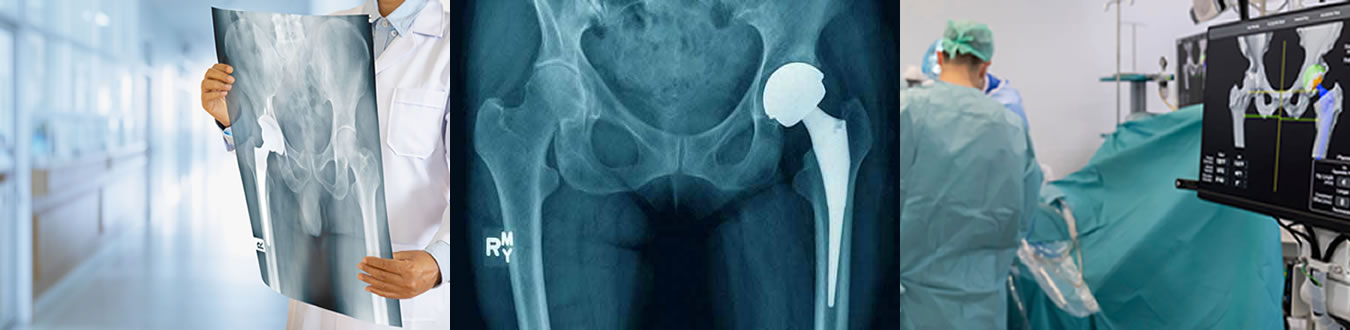

Ισχίο

αρθροπλαστική ισχίου

αναθεώρηση της αρθροπλαστικής ισχίου

κατάγματα ισχίου